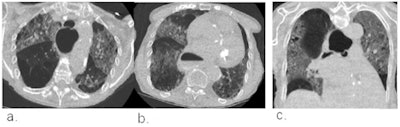

Schalekamp's team sought to evaluate the efficacy of using the CO-RADS system for chest CT in patients with moderate to severe symptoms of COVID-19. The system scores pulmonary involvement using a scale of 1 to 5 (1 = normal, 5 = typical for COVID-19). A score of 4 or higher is considered highly indicative of COVID-19.

The CO-RADS system showed comparable diagnostic performance to RT-PCR testing and the clinical reference standard, especially after patients had symptoms for 48 hours or more.